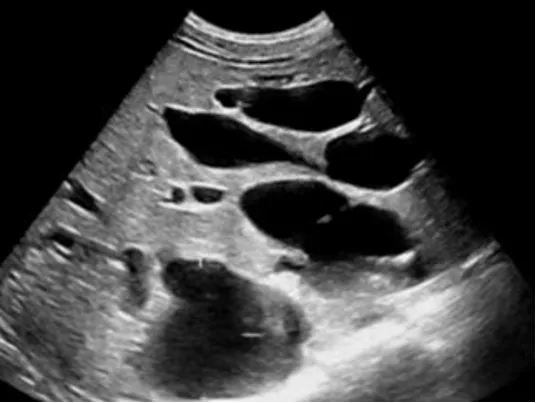

多囊肝

● 肝内无数个无回声区。

● 大者边界清,形态一般欠规整。

● 内透声好。

● 后方结构(后壁)回声增强。

● 无囊肿部位肝组织回声增强增粗。